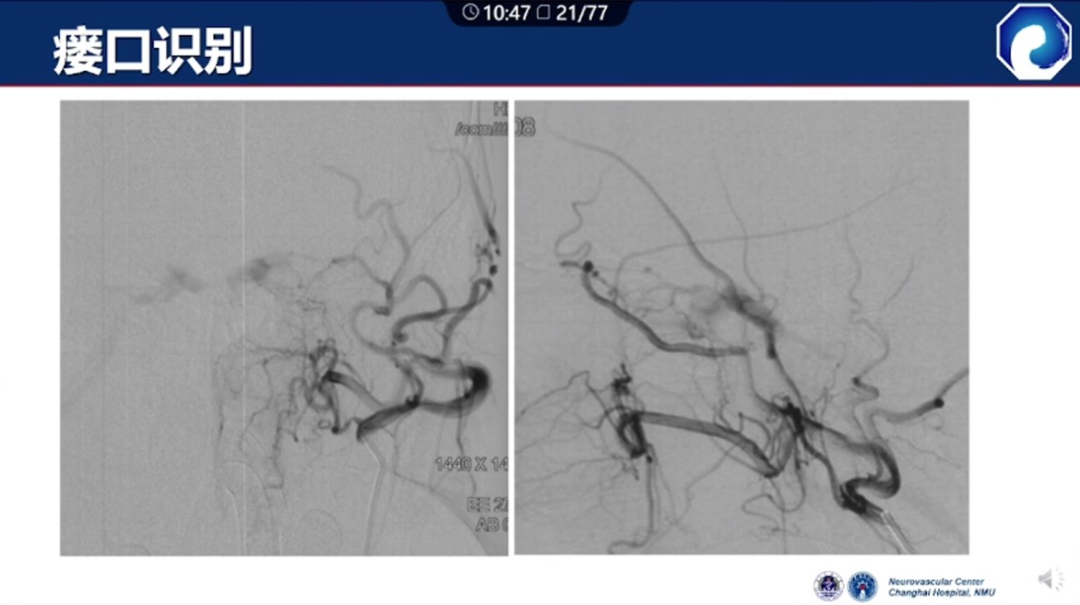

痿口静脉端的识别至关重要。

痿口静脉端精准完全闭塞是DAVF治愈的关键。